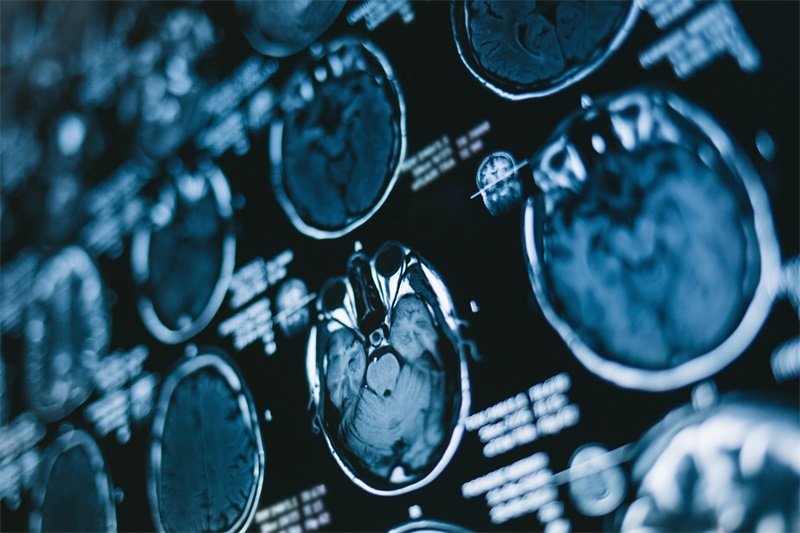

•影像学漏诊率高:常规CT扫描漏诊率达28%,需MRI冠状位薄层扫描才能清晰显示